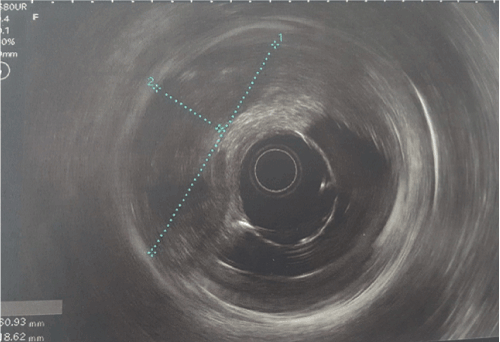

A 63 years old man with history of diabetes and hypertension, presented for bone pain. Pelvic X Ray showed multiple osteoconsensant lesions of the iliac wings, the sacrum and the femurs (Figure 1). CT scan objectified multiple hepatic metastases with a laterorectal mass (Figure 2). Colonoscopy showed aspect of extrinsic compression. Endoscopic ultrasound objectified a rectal mucosal lesion of 5x3,5 centimeters appearing in contact with the prostate (Figure 3) [1-5]. Histologically, hepatic biopsy confirmed a tumor proliferation that was made of two architectural aspects independent cells, and trabeculolobular classical endocrine architecture with expression of synaptophysin on immunochemistry [1-5] (Figure 4).

Figure 2. CT scan objectified multiple hepatic metastases with a laterorectal mass